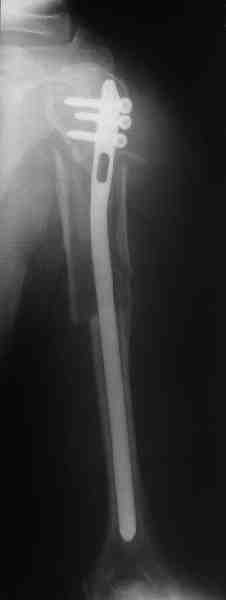

Прооперировали больную с переломом плеча все же гвоздем, Фото в приложении.

Гвоздик похоже ЦИТОвский?

Полагаю, бабушку можно поздравить с обретением

независимости. Судя по снимкам, неврологических расстройств нет и такая пациентка выпишется после снятия швов.

Только сформировали канал в головке. Диафиз не рассверливали. Хотя при необходимости, конечно, рассверлили бы.

Гвоздь большеберцовый нашей модификации, действительно, их делает предпричятие "ЦИТО". Тут взят 9 мм, укорочен до 240 мм, сделано дополнительное отверстие самое проксимальное, ну и для дистального винта.

Неврологии нет, а выписать можно хоть на второй день, швы можно снять и в местной больнице.

Почему так надолго? На ближэайшие недели - разработка движений, и все. Полагаю, что недель после 4 никаких рекомендаций не будет нужно, просто жить обычной жизнью сельской пенсионерки.